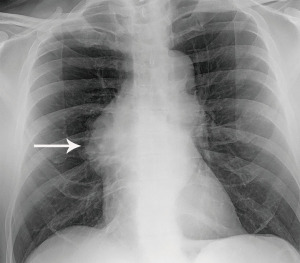

The most performed imaging examination is the routine chest radiograph which can be the first modality suggesting a thymic lesion. Thymic tumors may result in added soft tissue projecting over normal anatomic structures resulting in thickening of the anterior junction line or the “silhouette sign”. Normally air in the lungs delineates the soft tissue structures that abut the lung, such as the heart and mediastinum. Clear delineation of anatomic structures can be limited when a mass is present as soft tissue now abuts normal structure instead of air. This inability to distinguish one structure from another results in obscuration, or the “silhouette sign”. Lateral radiographs help confirm the presence of thymic tumors as they better demonstrate the prevascular space which is readily seen behind the sternum and is normally lucent. A mass in the prevascular space can form a convex contour abnormality when outlined by adjacent lung (Figure 1). Small prevascular lesions may not be radiographically apparent, however. Given the low sensitivity and specificity of radiographs, cross-sectional imaging is essential in the assessment of thymic tumors.